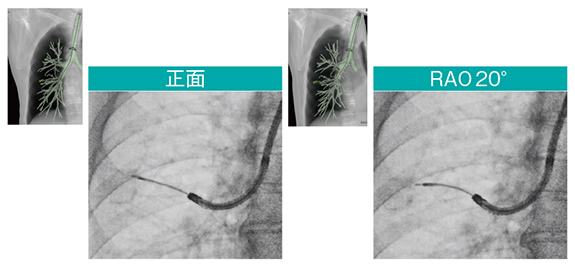

Cアームは病変とデバイスの位置関係の確認に有用であり、正面視ではデバイスと病変または胸膜の距離を反映していないケースでも、CアームをLAO/RAOに回転し、X線とデバイスの進行方向を直交させることで正確に位置関係を把握できる。

また、当院では3D画像解析システムを用いて事前シミュレーションを行っている。CT画像からバーチャルフルオログラフィを作成してCアームを回転させた際の病変と胸膜の距離を把握し、術中は検査室内でバーチャルフルオログラフィを確認しながら、医師がCアームの操作を行い手技を進める(図3、4)。正面視ではデバイスが到達しているように見えてもRAO20°では到達していないことがわかるケースもあり、Cアームの角度付けは重要である(図5)。また、病変へのデバイス到達が難しいと考えられた背側の腫瘤陰影症例において、LAOの角度をつけて背側縦隔側への穿刺のシミュレーションを行い、バーチャルフルオログラフィどおりに縦郭側に穿刺を行ったところ、吸引生検と同時にEBUSを挿入できた。

図3 バーチャルフルオログラフィを作成しCアーム角度を確認

図4 バーチャルフルオログラフィで確認したCアーム角度まで回転

図5 Cアームの角度付けによる透視像の比較

Accent適用、スコープ:BF-P290、ガイドシース:SG-400C、EBUS:US-S20-20R(オリンパス社製)